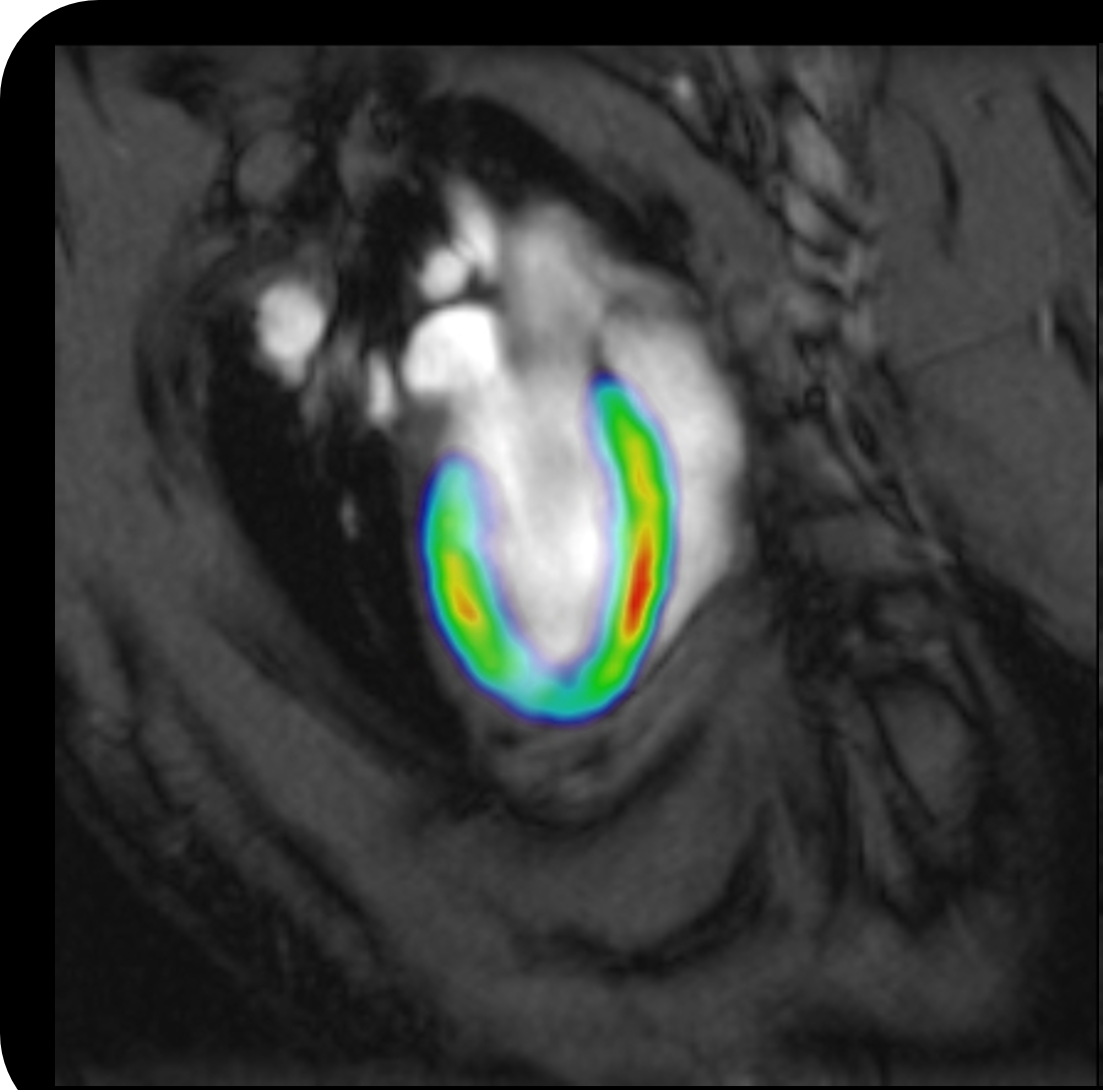

ブルカーでは、腫瘍学、神経医学、循環器医学、炎症、感染症、癌の研究、さらに機能や解剖学のための神経画像、整形外科、脳卒中モデルの研究などの様々な分野のための先進的な前臨床イメージングソリューションを提供しています。

私たちの提供する技術にはMRI(磁気共鳴イメージング)、PET(ポジトロン断層撮影法)、SPECT(単一光子放射形コンピュータ断層撮影法)、マイクロCT(マイクロコンピューター断層撮影法)、MPI(磁気粒子イメージング)などがあります。